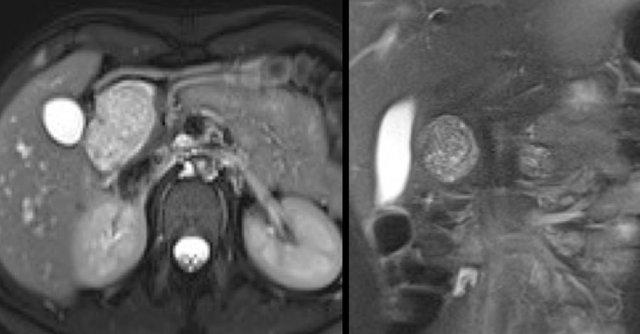

Một trường hợp IPMN thể ống nhánh khác phát hiện qua tầm soát với hai nốt (vòng tròn và mũi tên).

Chuỗi xung T1W xóa mỡ trước (hình bên trái) và sau tiêm thuốc tương phản từ (hình bên phải).

Siêu âm nội soi (EUS) có thuốc tương phản từ cho thấy 2 ổ không ngấm thuốc, nhiều khả năng là nút nhầy.

Sau 6 năm theo dõi, nang không thay đổi.

Nam giới 75 tuổi với IPMN ống nhánh kích thước 2,7 cm tại đầu tụy (vòng tròn).

Trong quá trình theo dõi một năm sau, phát hiện giãn ống tụy chính.

Siêu âm nội soi (EUS) cho thấy ung thư biểu mô tuyến còn khả năng phẫu thuật cắt bỏ.